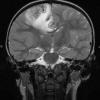

HSV-I Encephalitis (2)